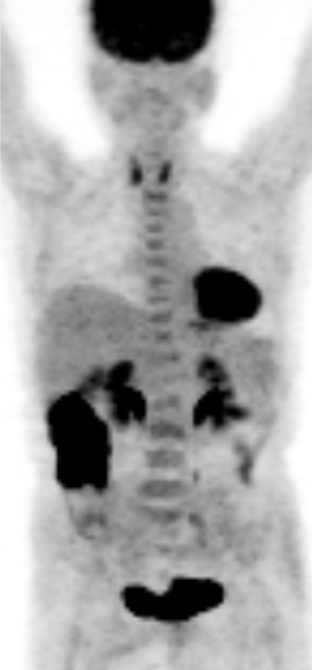

a. PET MIP像

b. PET/CT像

c. CT像、化学療法後

d. PET MIP像

e. PET/CT像

f. CT像

図2 悪性リンパ腫治療効果判定:完全寛解 化学療法前